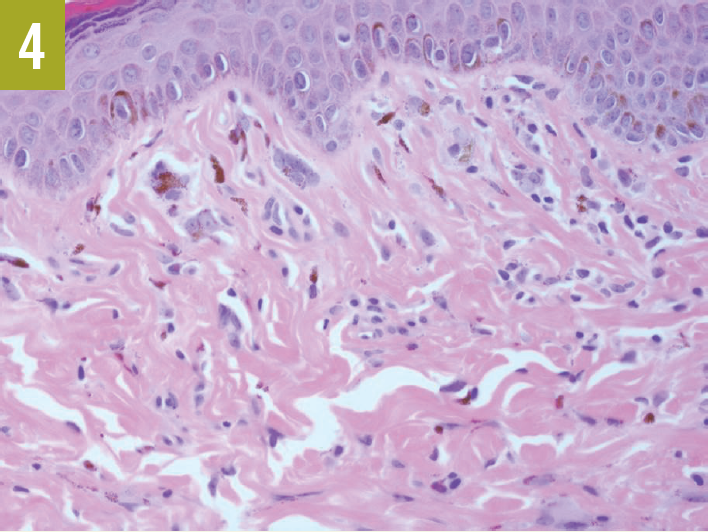

Several of the largest facial lesions were removed. Biopsy results confirmed the lesions to be angiofibromas, thereby confirming the TSC diagnosis (Figures 3 and 4).

Figure 4. Higher-power magnification (x400) revealed the thickened collagen bundles and stellate fibrocytes that are characteristic of an angiofibroma.